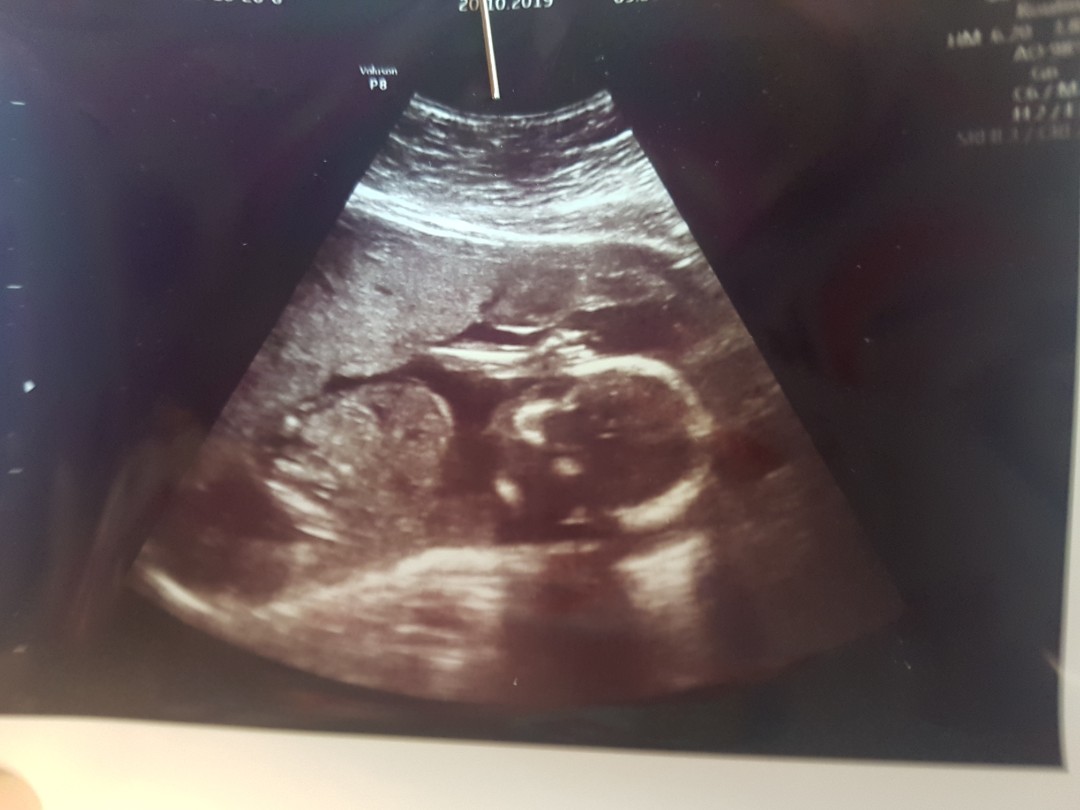

ตอน5เดือนค้า

ตอน18วีคจ้า

ตอน5เดือนค่ะ